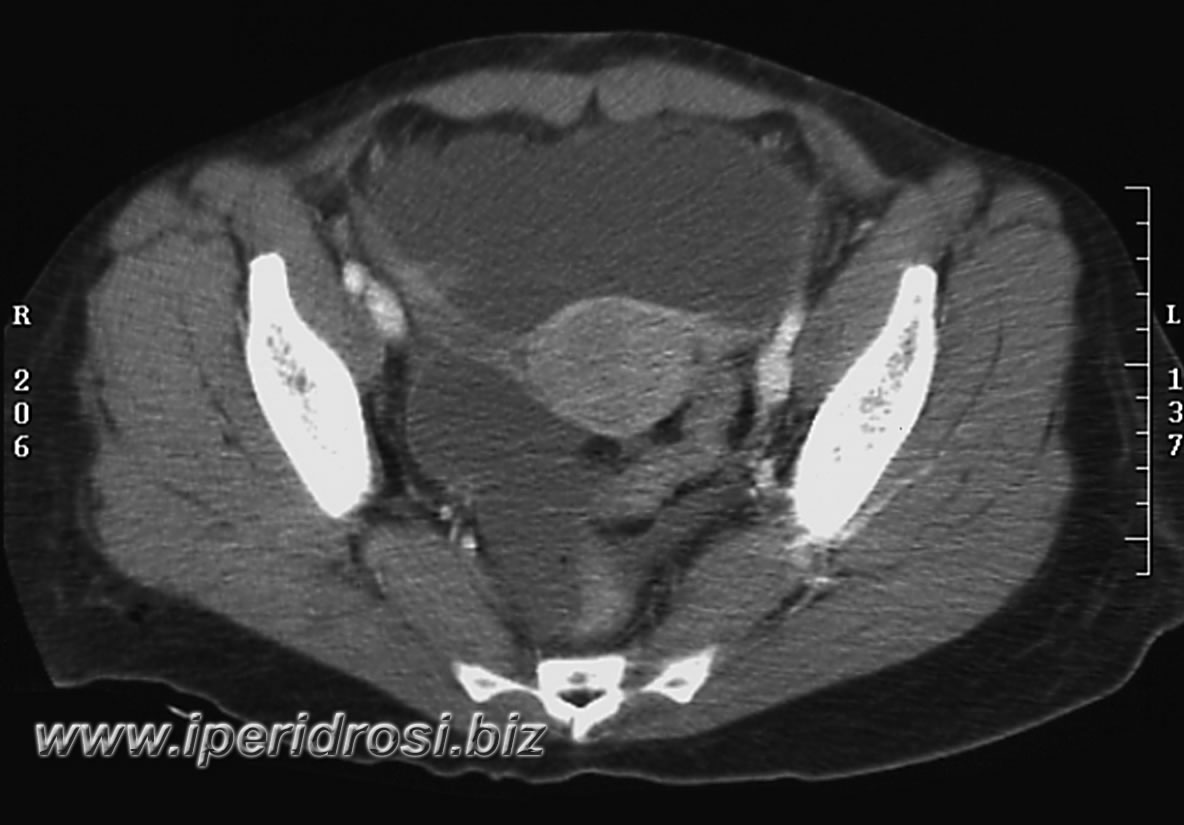

Torace: a sinistra abbondante versamento pleurico e parzialmente saccato, atelettasia parenchimale basale bilaterale più evidente a sinistra dove residua limitato parenchima ventilato.

Addome: abbondante versamento addomino-pelvico diffuso con falda aerea piuttosto abbondante all'addome superiore. Rene a ferro di cavallo con cisti parapieliche a sinistra. Distensione del colon da meteorismo ed ispessimento delle pareti intestinali con iperemia di numerose anse.